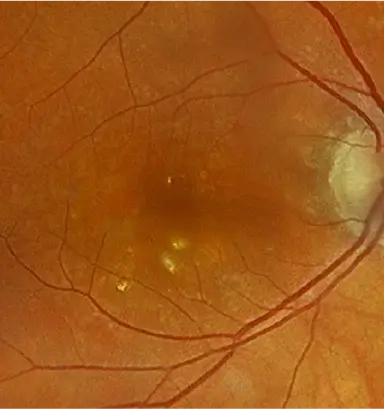

IZERVAY™ (avacincaptad pegol intravitreal solution) is indicated for the treatment of geographic atrophy (GA) secondary to age-related macular degeneration (AMD)